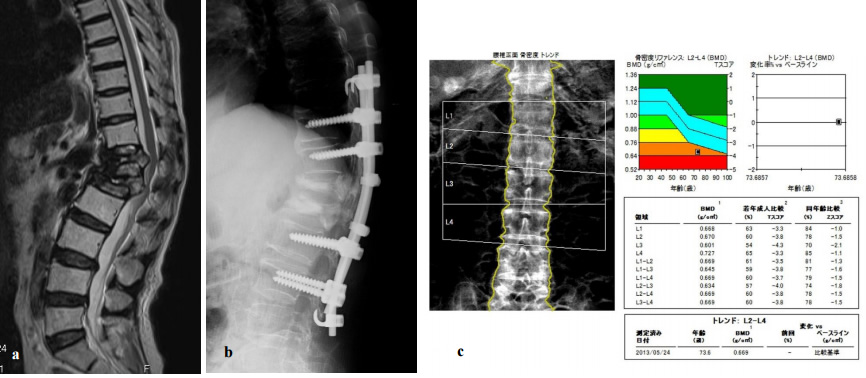

図1. 92歳女性、第12胸椎骨折例

特に外傷なく腰痛を自覚し単純X線では明らかな骨折を認めず(a)、

MRI脂肪抑制画像で第12胸椎椎体の信号変化を認め骨折と診断した (b)。

上位腰椎におけるDXAではYAM値57%と高度な骨粗鬆症であった (c)。